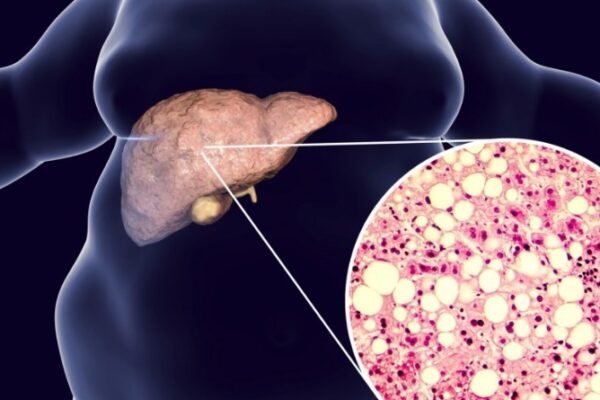

Recomienda IMSS Veracruz Norte alimentación saludable para prevenir hígado graso

Con el objetivo de prevenir complicaciones en la salud y mantener una saludable función hepática, el Instituto Mexicano del Seguro Social (IMSS) en Veracruz Norte recomienda adoptar una alimentación saludable que evite desarrollar hígado graso. La nutrióloga clínica del Hospital General de Zona (HGZ) No. 11, Norma Seseña de la Cruz, comentó: “una dieta equilibrada,…